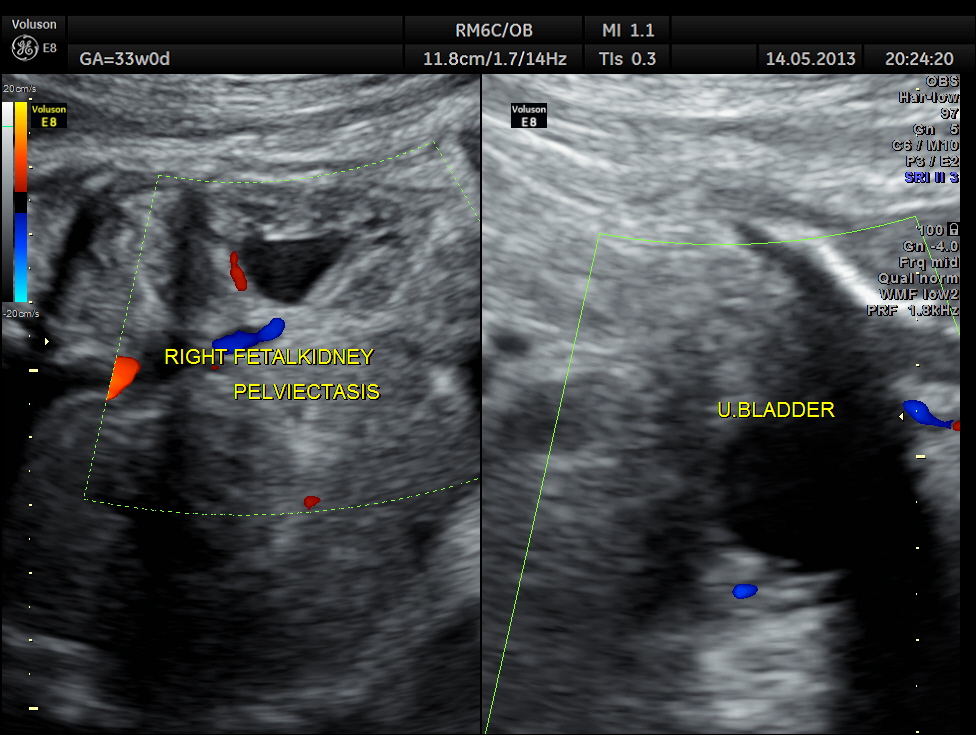

This was distinct from the urinary bladder and the kidneys. Both the kidneys showed mild pelviectasis.